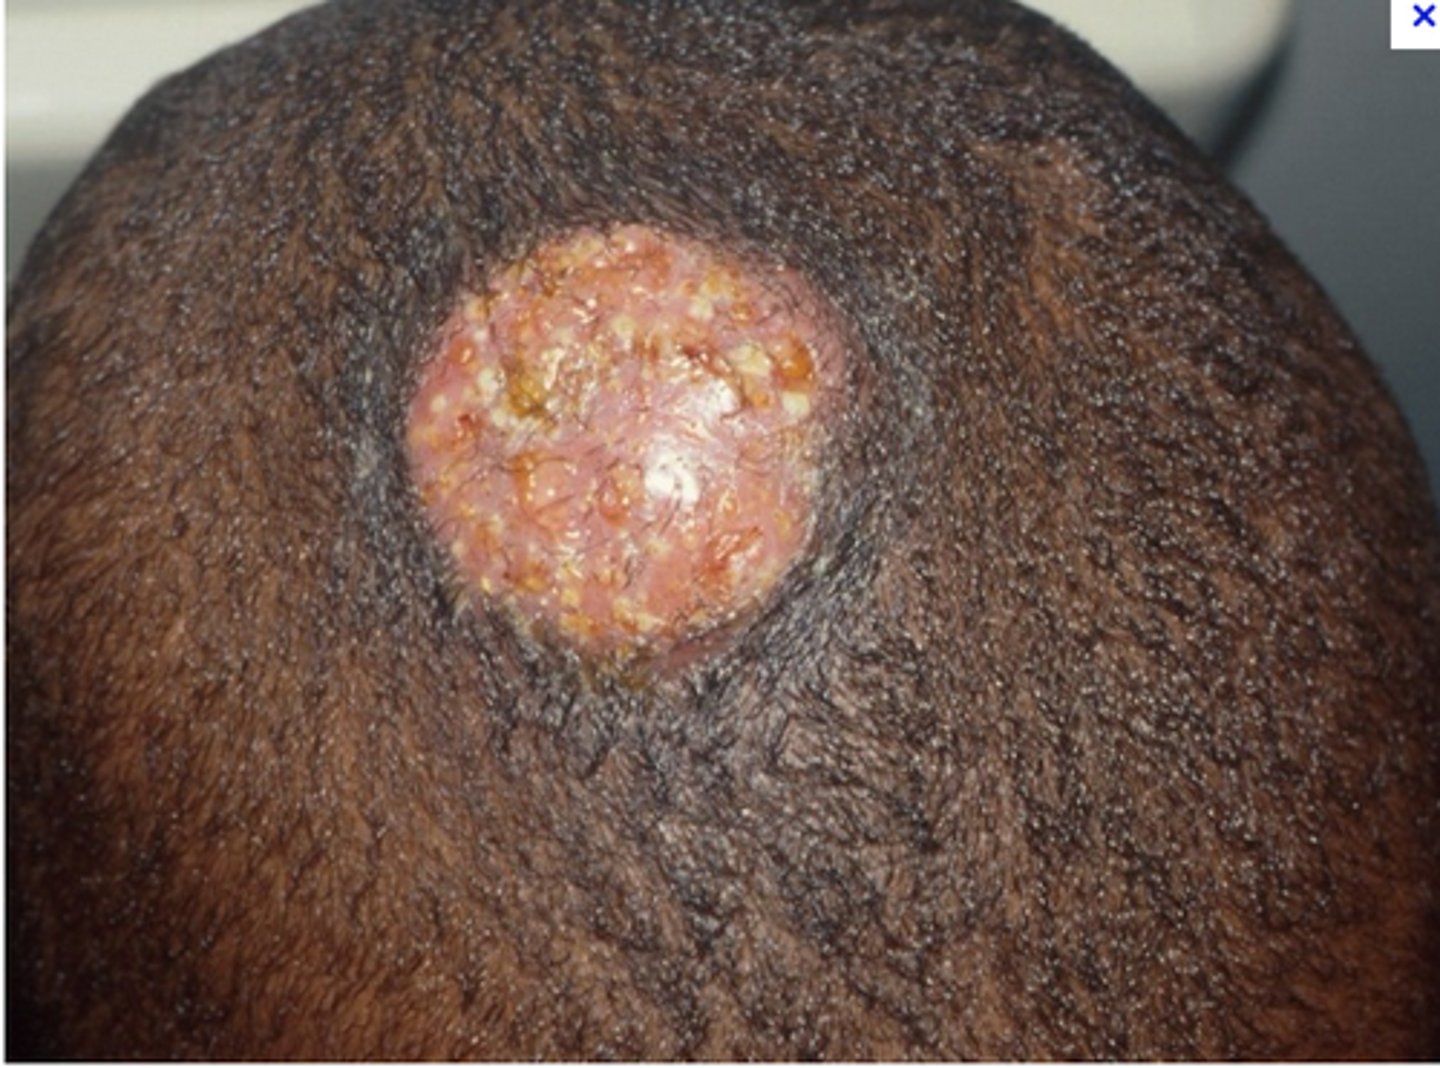

Tinea Capitis

ringworm, fungal infection of the scalp